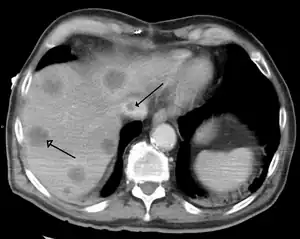

Budd–Chiari syndrome secondary to cancer, note clot in the inferior vena cava and the metastasis in the liver